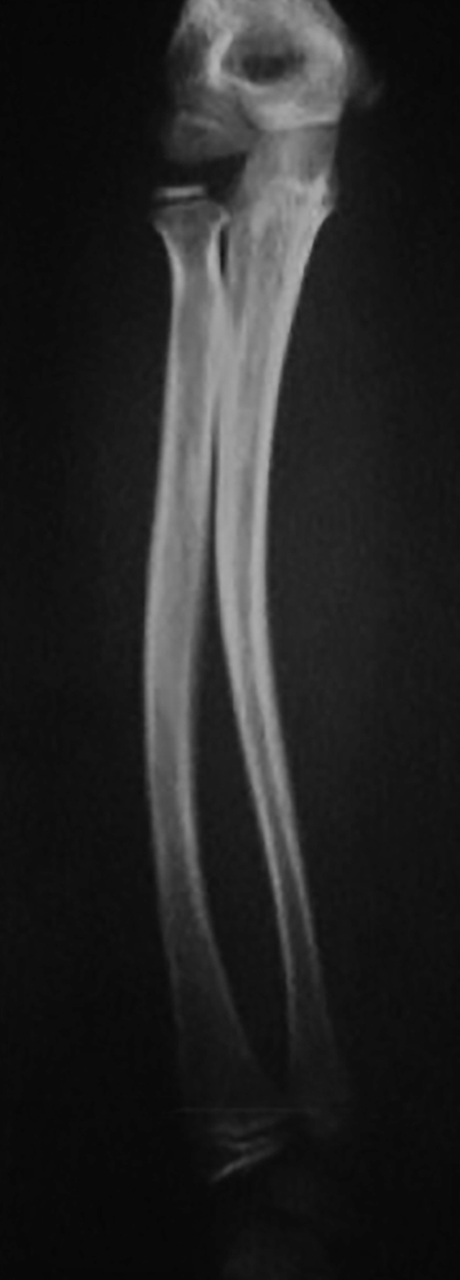

Quel est votre diagnostic ?

Il s'agit de l'aspect radiologique d'une fracture plastique chez l'enfant. Si certaines fractures sont proches de celles rencontrées chez l'adulte, d'autres sont en revanche spécifiques à l'enfant : fractures en motte de beurre, fractures en bois vert, déformation plastique, fractures sous-périostées, décollements épiphysaires. L'os de l'enfant est moins résistant que celui de l'adulte mais il n'y a pas de fracture sans traumatisme, donc pas de fracture avant l'âge de la marche. Le bilan radiographique comprend des clichés avec des incidences de face et de profil, englobant les articulations sus- et sous-jacentes. Les clichés comparatifs ne sont pas nécessaires. Ces clichés sont réalisés après antalgie efficace (paracétamol et anti-inflammatoires non stéroïdiens). La fracture plastique est une incurvation pathologique de la diaphyse, sans rupture corticale, qui survient lorsque les capacités élastiques de l'os sont dépassées. L'ulna et la fibula sont les os les plus souvent concernés. Le traitement est orthopédique, par une immobilisation plâtrée pour une durée de 3 semaines. La radiographie de contrôle n'est pas systématique.